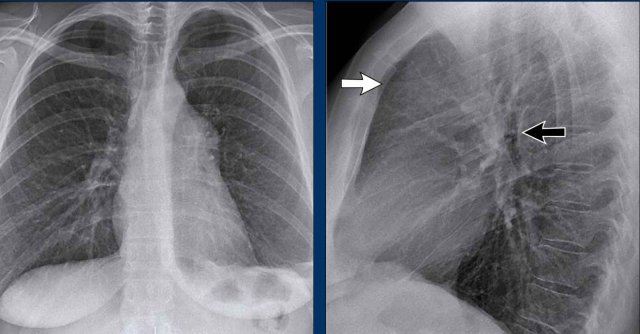

Clinical Case

A 70-year-old male patient presents following a fall down the stairs, complaining of severe right flank pain.

Imaging Findings

- On the PA chest radiograph, there is an absence of the right fifth digit.

- On the lateral view, there is increased density projected over the lower thoracic spine.

What is your diagnosis?

The findings are consistent with right lower lobe atelectasis.

On the PA view, note the abnormal contour of the right heart border. The right interlobar pulmonary artery is not visualized—this is because it is not surrounded by aerated lung, but rather by the collapsed right lower lobe, which lies adjacent to the right atrium.

On follow-up imaging, the right lower lobe has re-expanded, and the atelectasis has resolved.

This suggests that the atelectasis was likely due to post-traumatic hypoventilation with mucus plugging.

Also noted on the follow-up radiograph is the reappearance of the right fifth finger (black arrow), and restoration of a normal right heart border (white arrow), confirming re-expansion of the lower lobe.